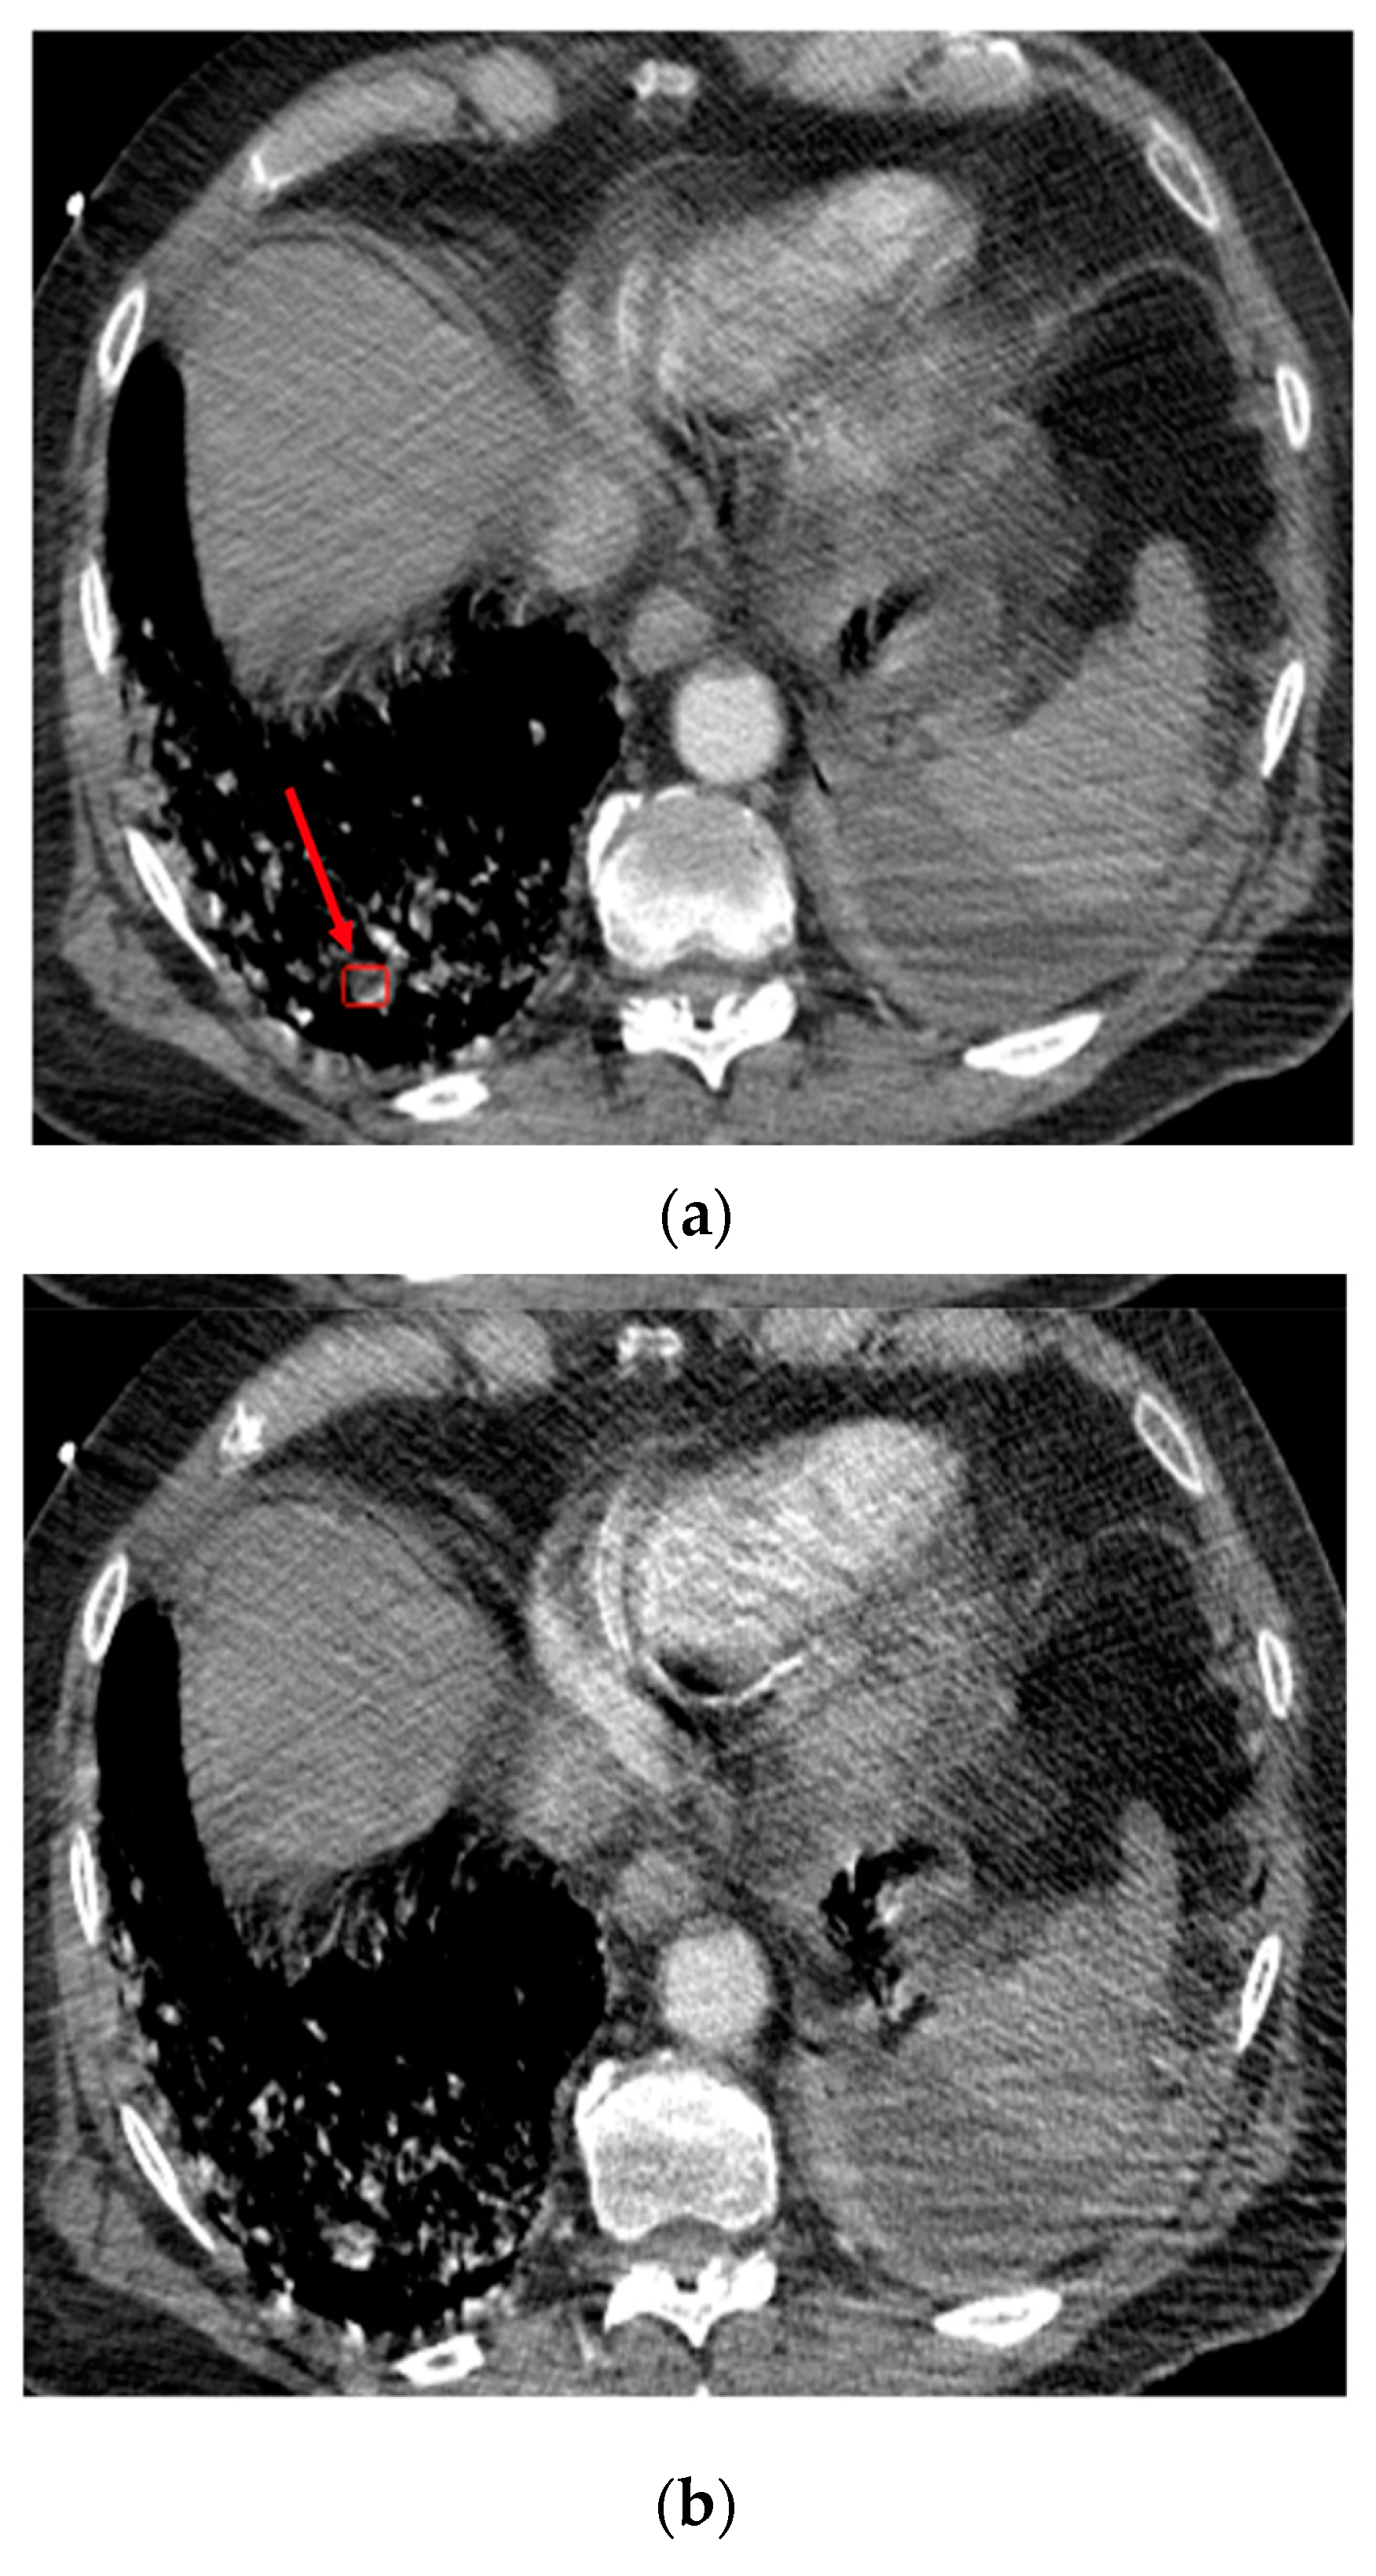

A total of 17/201 (8.5%) cases were false positives. Among them, six cases were complicated cases and were the subject of disagreements between the experts. Six PEs were correctly detected within subsegmental arteries, but these were the cases considered as “negative” by the readers, since the application was not designed/trained to flag subsegmental arteries. The other false positives were due to the presence of important noise, streak and/or motion artifacts (Figure 4), or the partial volume effect artifact. The location and cause of the false positives are reported in Supplementary Materials—Table S3.

Figure 4.

Case of the false positive response of the algorithm in the right lower lobe. Top (a): Axial image at the level of lung bases. The red arrow shows the pseudo-lesion. Bottom (b): Subsequent axial image showing motion artifacts blurring the pseudo-lesion.